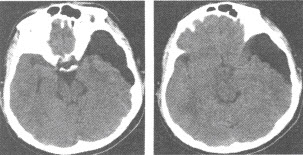

男,15岁,CT检查如图,最可能的诊断为()

A:正常

B:脑萎缩

C:脂肪瘤

D:蛛网膜囊肿

E:硬膜下积液